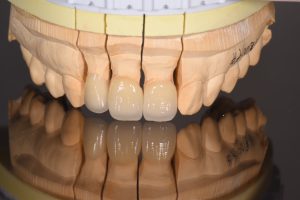

完成した被せ物

歯肉の下までしっかり型取りするために、圧排コードを用いてシリコン印象で製作したemaxクラウン。

右上2番目は大きな虫歯があったため根管治療を行った。